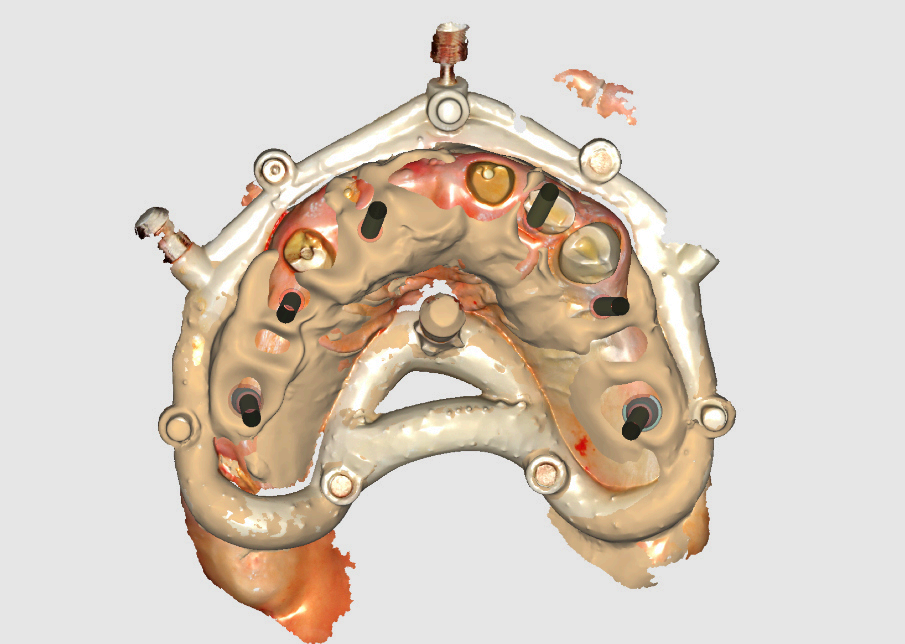

Following implant placement, intraoral photogrammetry was performed using the Shining3D Elite scanner. Scan markers were attached to the MUAs, and their positions were captured with high precision (Fig. 2.4, 3.4). Multiple scans were acquired, including the maxillary arch (Fig. 3.1), the fxation bar from the stackable guide (Fig. 3.2), the MUAs (Fig. 3.3), and the surrounding soft tissues (Fig. 3.5). The photogrammetry data was merged with conventional intraoral scans, using the fxation bar as a fduciary to align all datasets accurately (Fig. 3.7). A heat map generated in the software confrmed the precision of this alignment, with minimal discrepancies across the arch (Fig. 3.7). The scan markers were then converted to implant-specifc analogs compatible with the chosen implant system (Fig. 3.6).

Group 3: Digital Scanning Fig. 3.1: Full maxillary scan prior to merging. Fig. 3.2: Scan of the fxation bar from the stackable guide as a fduciary reference. Fig. 3.3: Scan showing MUAs in position. Fig. 3.4: Photogrammetry scan markers captured intraorally. Fig. 3.5: Composite scan integrating photogrammetry markers with soft tissue data. Fig. 3.6: Conversion of scan markers to implantspecifc analogs. Fig. 3.7: Heat map illustrating scan alignment accuracy post-merging. Fig. 3.8: Design of the provisional prosthesis with screw channel holes.